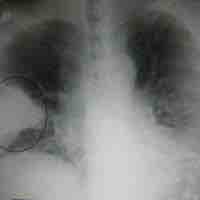

Tuberculosis is a common, and in many cases lethal, infectious bacterial disease that mainly affects the lungs.

Pneumonia is an inflammatory lung disease that can lead to problems with breathing, often caused by bacterial infections.

Viral pneumonia, one of the two leading causes of pneumonia, more commonly affects children.

Pneumocystis pneumonia (PCP) or pneumocystosis is a form of pneumonia, caused by the yeast-like fungus Pneumocystis jirovecii.

Blastomycosis is a fungal infection caused by the organism Blastomyces dermatitidis.